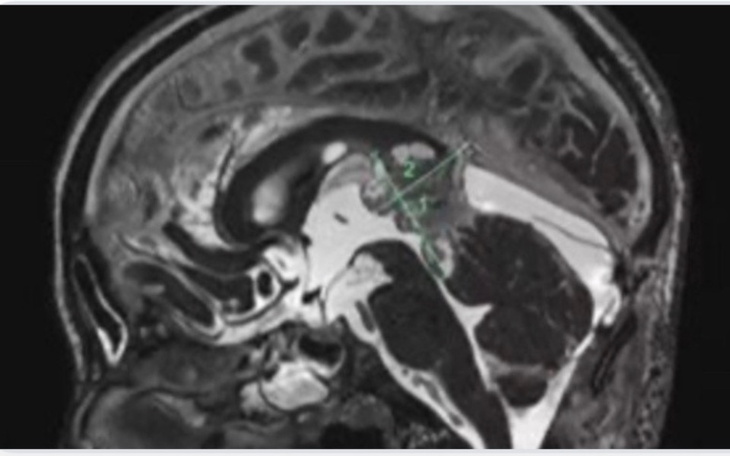

Złoslowy guzem mózgu. Straszną diagnozę postawili niemieccy lekarze. Bóle głowy i nudności doprowadzily do wizyty w szpitalu. Przeprowadzono badanie rezonansem, które pokazało, że w głowie jest guz.

Pobrano próbki guza do badania. Okazało się, że jest szybko rosnący guz umiejscowiony na rozwidleniu dwuch żył.